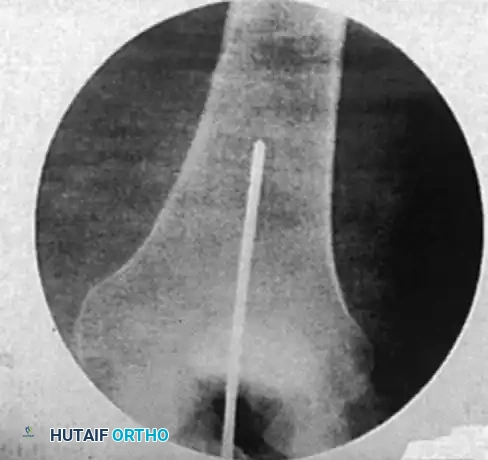

Confirm the reduction and the guidewire position with multiplanar fluoroscopy. The ultimate goal is concentric, central placement of the wire in the distal femur, terminating exactly at the level of the epiphyseal scar (or the midportion of the patella on an AP view).

Image

Intramedullary bead-tipped guidewire inserted concentrically to the distal femur at the level of the distal femoral physeal scar.